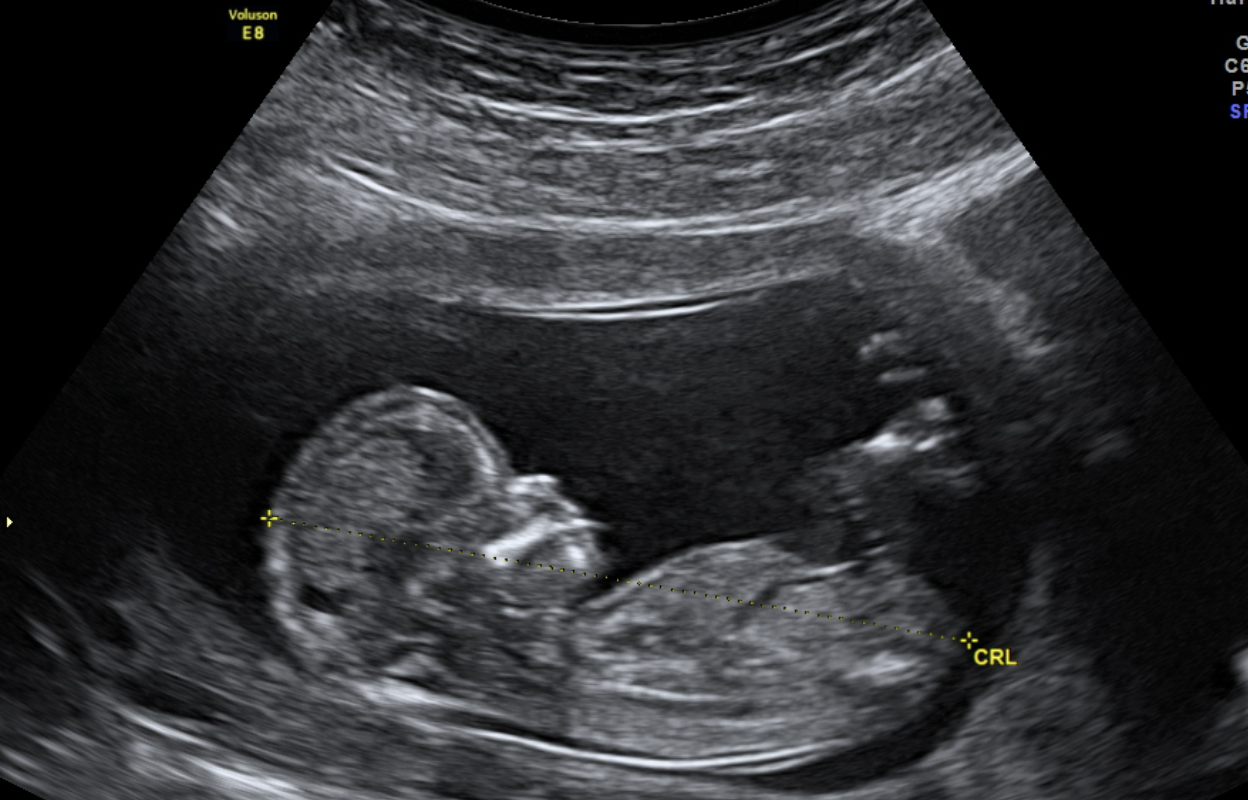

Challenge: A safe, full-term pregnancy is vital to the health and wellbeing of every child, yet it is far from guaranteed. Preterm birth (PTB) is the leading cause of perinatal death and remains a major global health concern. Due to limited pregnancy-related research, clinicians cannot fully explain what triggers healthy, gestationally-appropriate labor, let alone risky premature labor. This lack of fundamental understanding hinders the ability to predict PTB on an individual patient level. This work focuses on the cervix, a complex biomechanical barrier in pregnancy. Sonographic measurement of cervical length with transvaginal ultrasound (TVUS) is a common clinical test to assess the risk of subsequent PTB.

Manual segmentation methods are usually time consuming, not scaleable, and can vary between clinicians and sonographers. Therefore, the researchers chose to adopt an automatic deep learning based multi-class residual UNet architecture segmentation method.

Findings: The researchers demonstrated that the standard-of-care TVUS may be used to accurately segment cervical geometry, enabling the study of cervical variations across pregnancies with broader implications in understanding and ultimately preventing PTB. Given that accurate sonographic cervix segmentation followed by multi-dimensional cervical geometric feature extraction is can have a higher PTB predictive capability compared to sonographic cervical length alone.